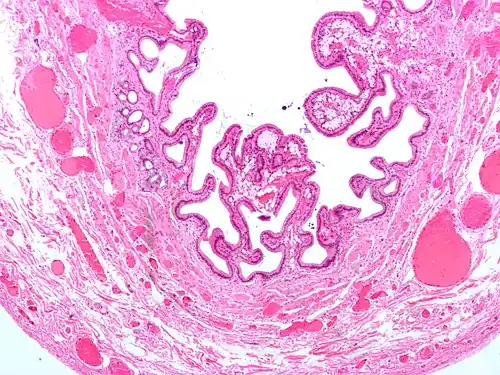

Micrograph of cholesterolosis of the gallbladder -

Micrograph of cholesterolosis of the gallbladder